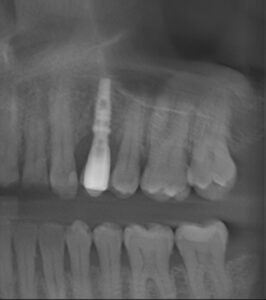

Panoramic reconstruction

Image 2. Mesio-distal cross sections of UL4 implant